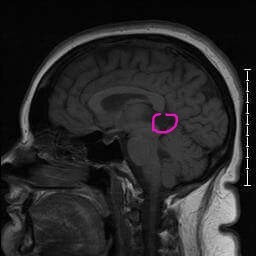

I have struggled with severe 'migraines' my entire life. They are debilitating. In August 2013, I went to the ER after multiple symptoms culminated in me falling from severe dizziness. I spent three days in the emergency room and after multiple tests, I was told that I had a 2.4cm pineal cystic tumor in my brain, but that it was not causing my symptoms, and I was dismissed with no other explanation.

I dealt with these symptoms for over 2 years and countless ER visits before a follow up CT showed that the cyst had grown to 2.7cm. After additional testing, it was discovered that while my cyst had grown a little, I also have severe venous sinus stenosis of the right dominant transverse, as well as empty sella syndrome. I was also given a positive diagnosis of Intracranial hypertension after a lumbar puncture showed high opening pressure.

These are not common conditions, and not a lot is known about them. Basically, the pressure inside my brain has increased above normal limits (IIH), my pituitary gland is flattened or abnormally filled with spinal fluid (empty sella syndrome), and the main sinus, or passageway, in my brain that blood and cerebral spinal fluid flow through is nearly closed completely. This puts me at extreme high risk of stroke, blood clots, aneurysm, seizures, and even blindness.

I have also been contacted by a world famous neurosurgeon regarding a second opinion on my pineal cystic tumor. He wants me to do an in person consultation to determine whether the cyst is causing any of my symptoms, and whether or not it should be surgically removed. It is far larger than average pineal region tumors and has shown growth in a short period of time, so it is imperative that I get attention from the best for my future. However, Dr. Kim works at a hospital in Houston, TX, so I need to find a way there to meet with him in March for the consultation.